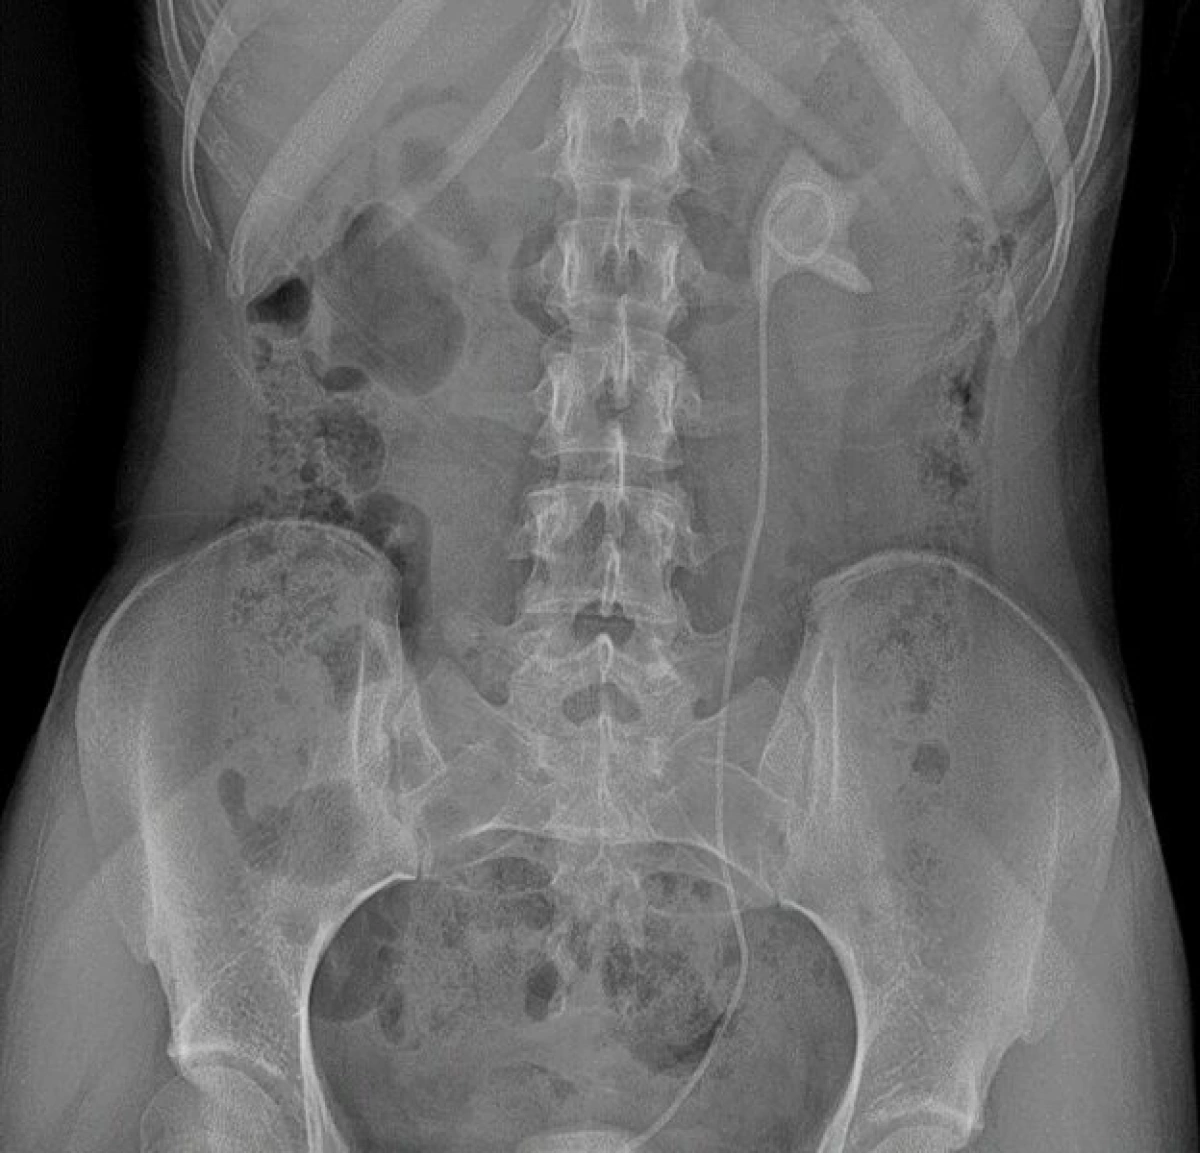

Непростой, но успешный курс лечения юной больной завершился во втором урологическом отделении клинической больницы №9.  Девушка поступила сюда с серьёзным комплексом осложнений. В другой больнице в связи с некупируемой почечной коликой ей был установлен мочеточниковый стент. Однако в установленный срок через 6 недель после операции пациентка не пришла для его удаления и в дальнейшем у врачей не наблюдалась. В результате стент оставался в организме целых 6 месяцев, как следствие — произошло отложение солей и формирование камней в мочевом пузыре и почке. Такое сочетание значительно усложнило клиническую картину и потребовало комплексного подхода к лечению. Девушке требовалась операция. На помощь пришла команда талантливых урологов клинической больницы №9. С помощью новейшего оборудования они провели две высокотехнологичные операции.

Первая операция — контактная цистолитотрипсия с использованием гольмиевого лазера. Этот метод позволил с высокой точностью раздробить камень в мочевом пузыре, минимизировать повреждение тканей и одновременно проработать область, затронутую длительным нахождением стента.

Вторая операция была также выполнена с помощью гольмиевого лазера для безопасного удаления стента, устранения последствий его длительного нахождения в организме, работы с камнем в почке — дробление и удаление.